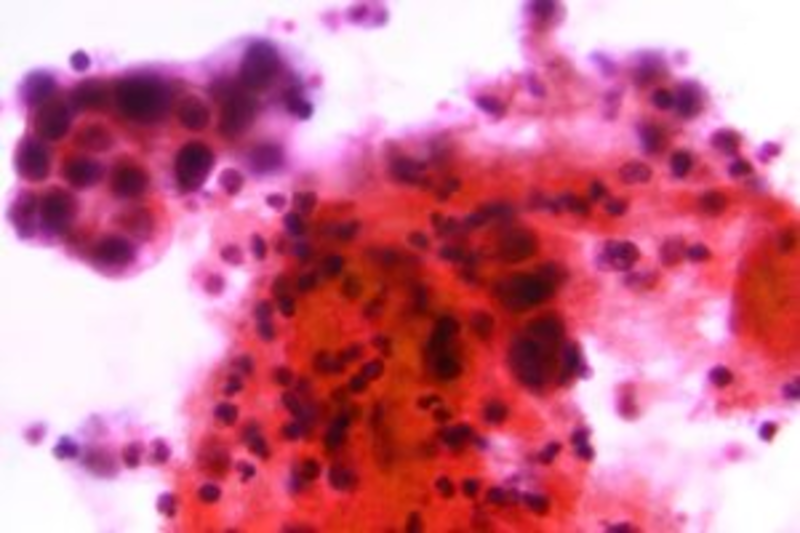

Type 2 endometrial cancer is increasingly difficult to treat, as there are limited warning signs. Per the study published in the journal JAMA Oncology, this aggressive kind comprised about 20% of cases and 45% of deaths.

While obesity may contribute to the less aggressive cancer, there are no clear indicators nor possible screening tests for Type 2 endometrial cancer. Irregular bleeding may be a factor, but many diseases or complications can also be attributed to the symptom.